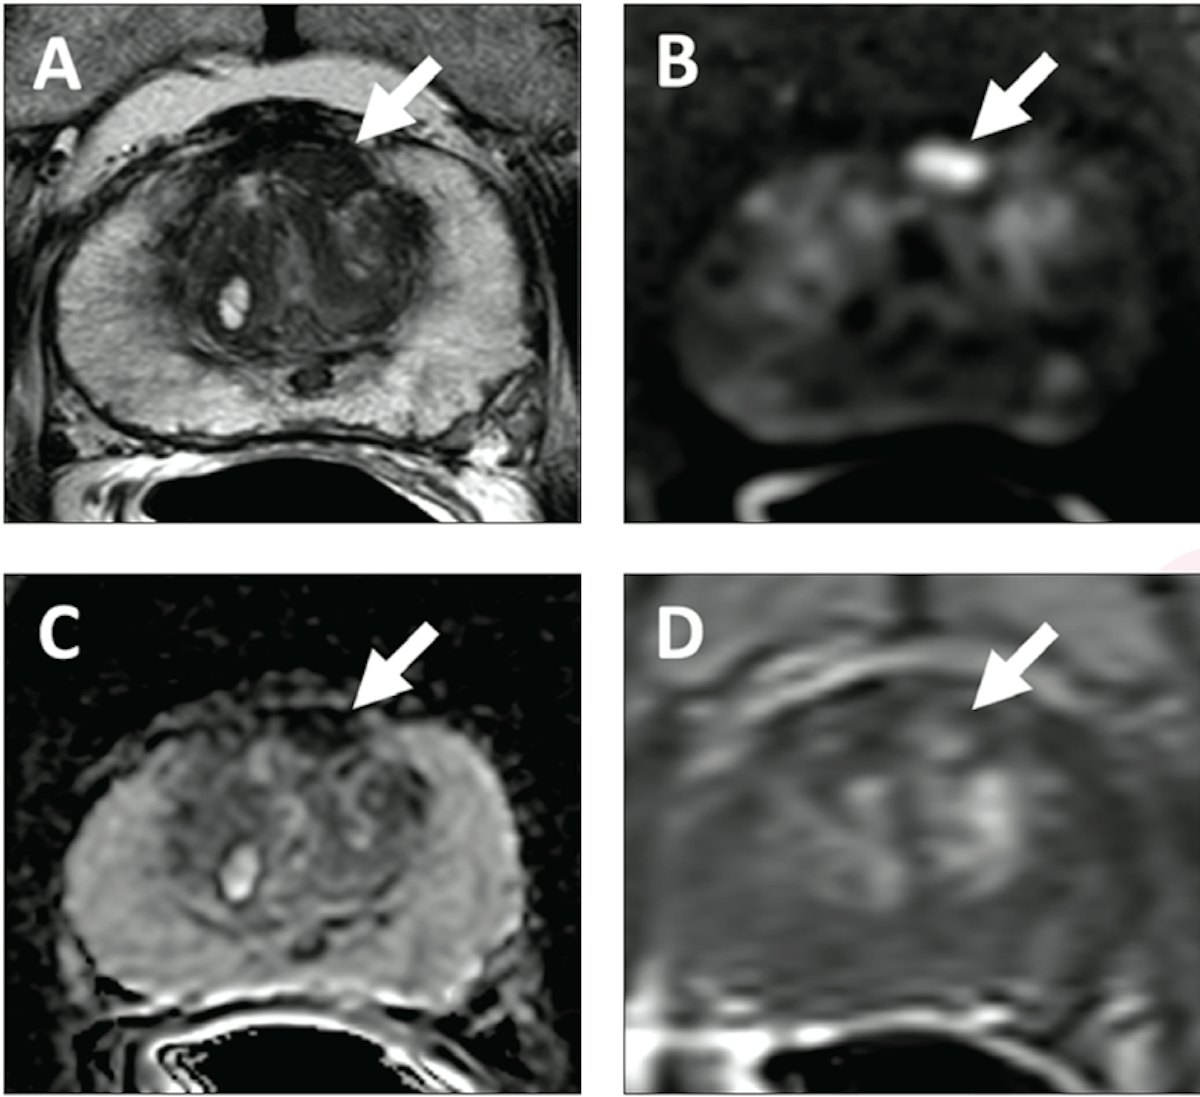

Pi rads v